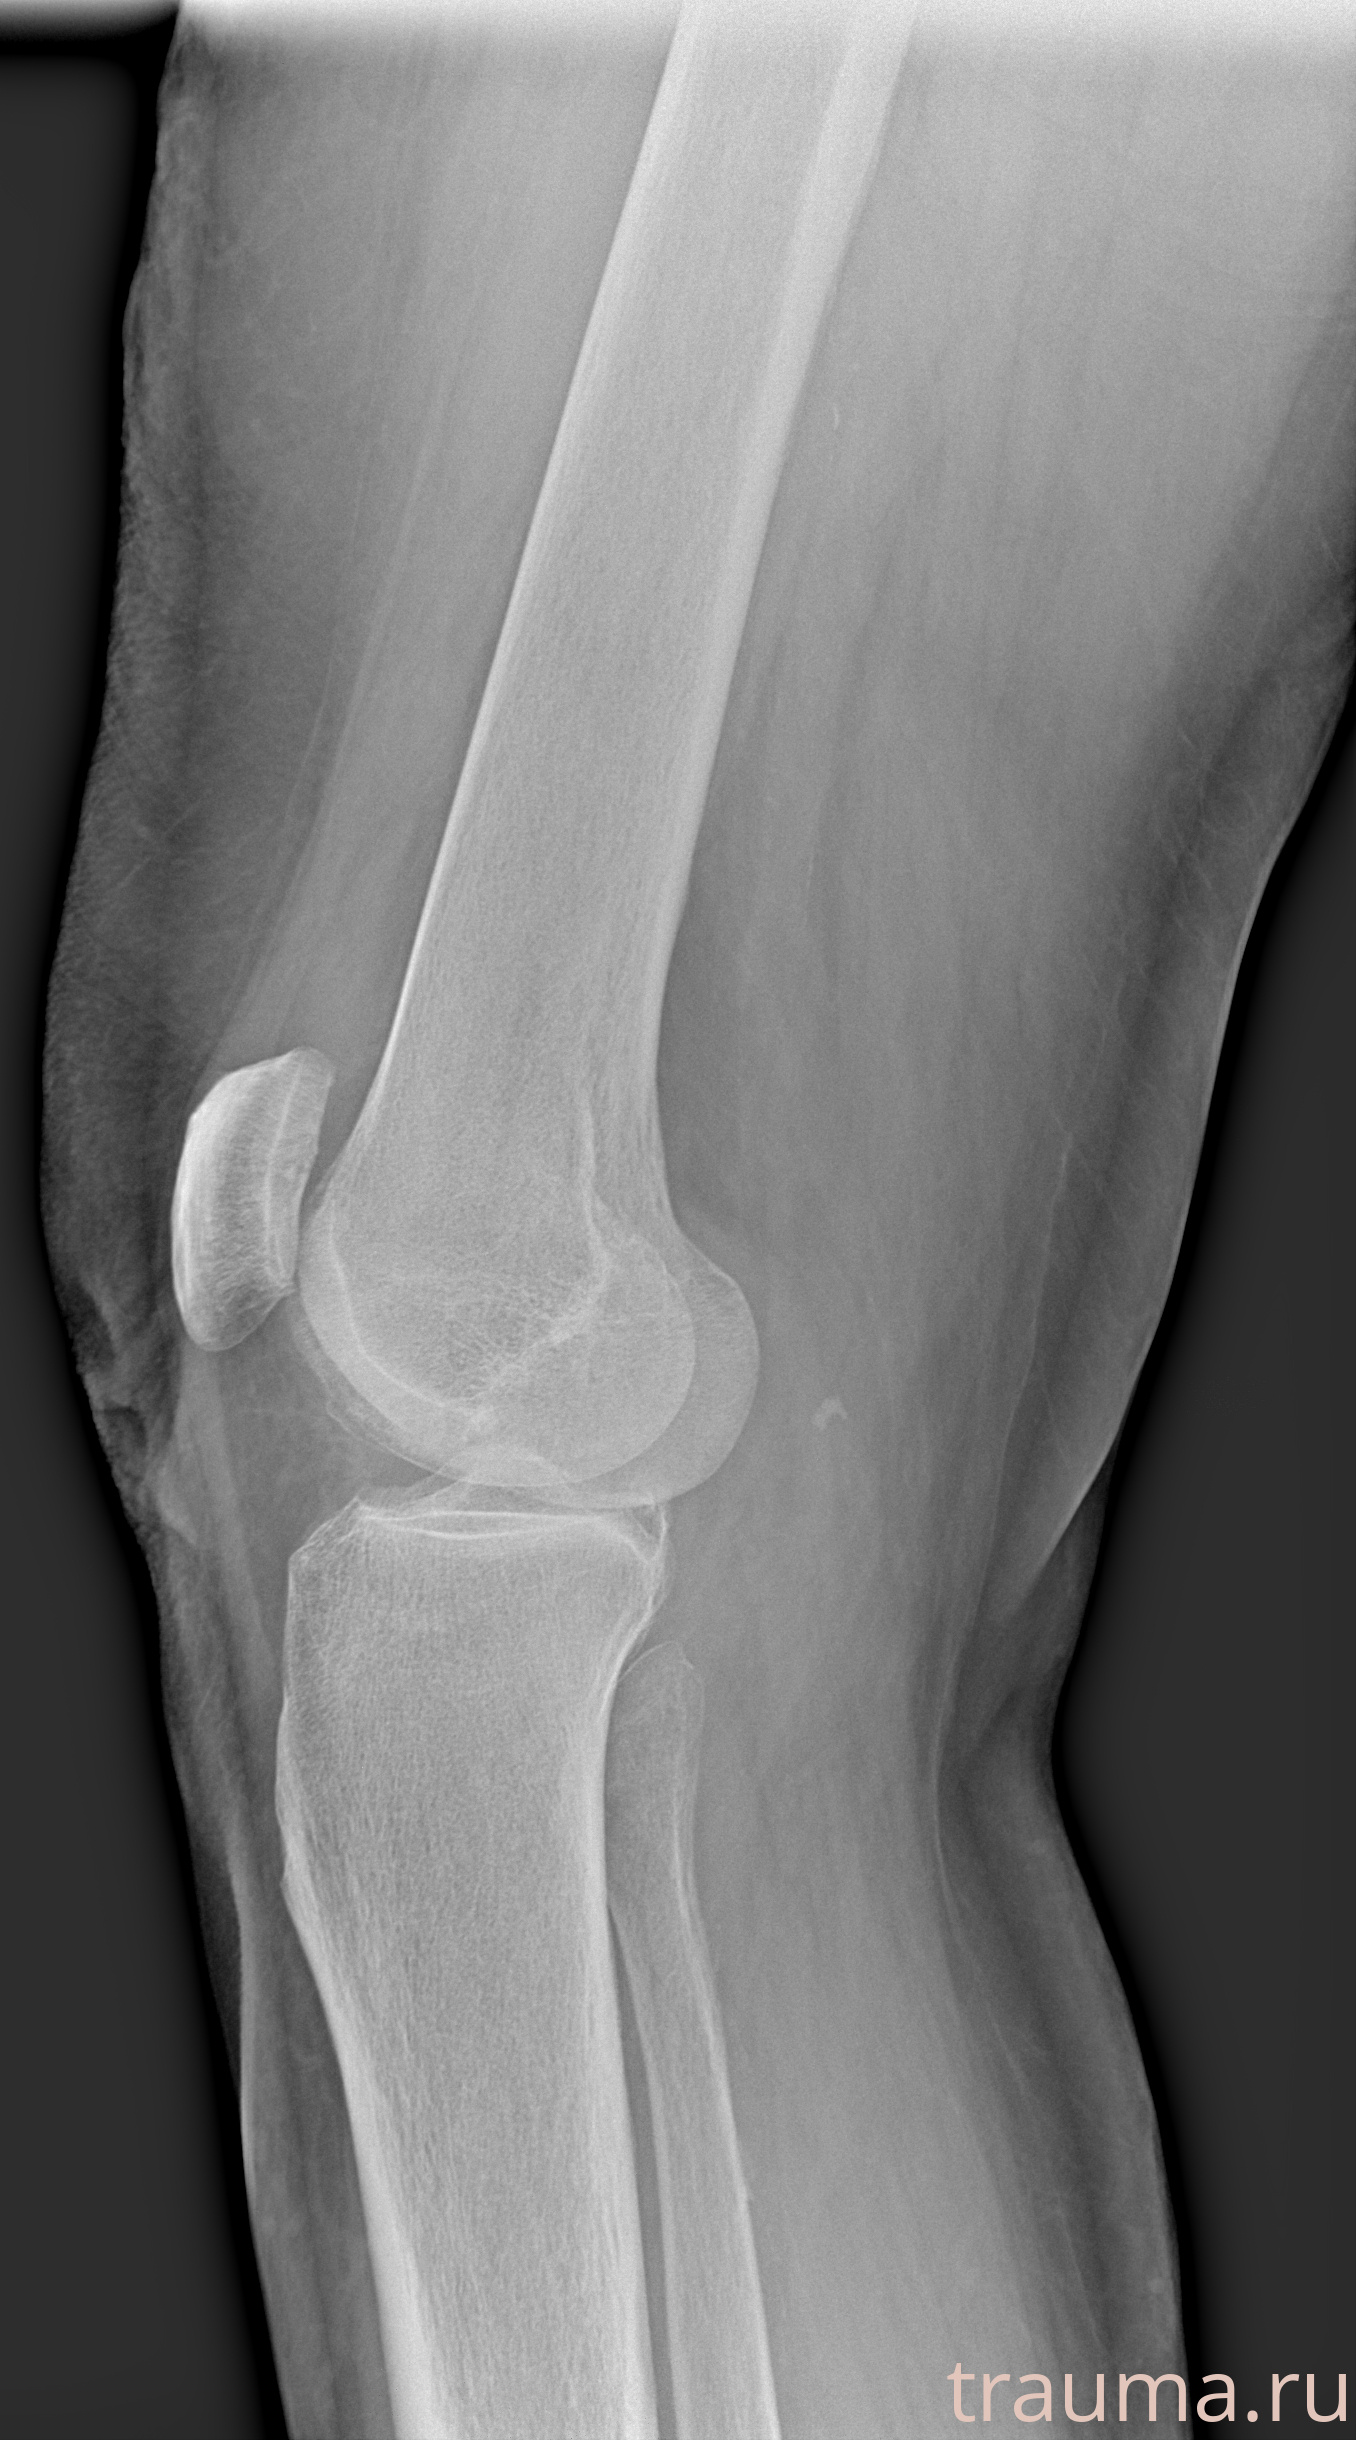

Рентген на дому: по вашему адресу приезжает врач-рентгенолог, травматолог-ортопед с мобильным рентгеновским аппаратом, проводит диагностику травмы или заболевания, делает необходимые рентгенограммы, дает рекомендации по дальнейшему лечению. Получить качественные снимки в домашних условиях возможно благодаря уникальной методике, разработанной МосРентген Центром для института  Склифосовского